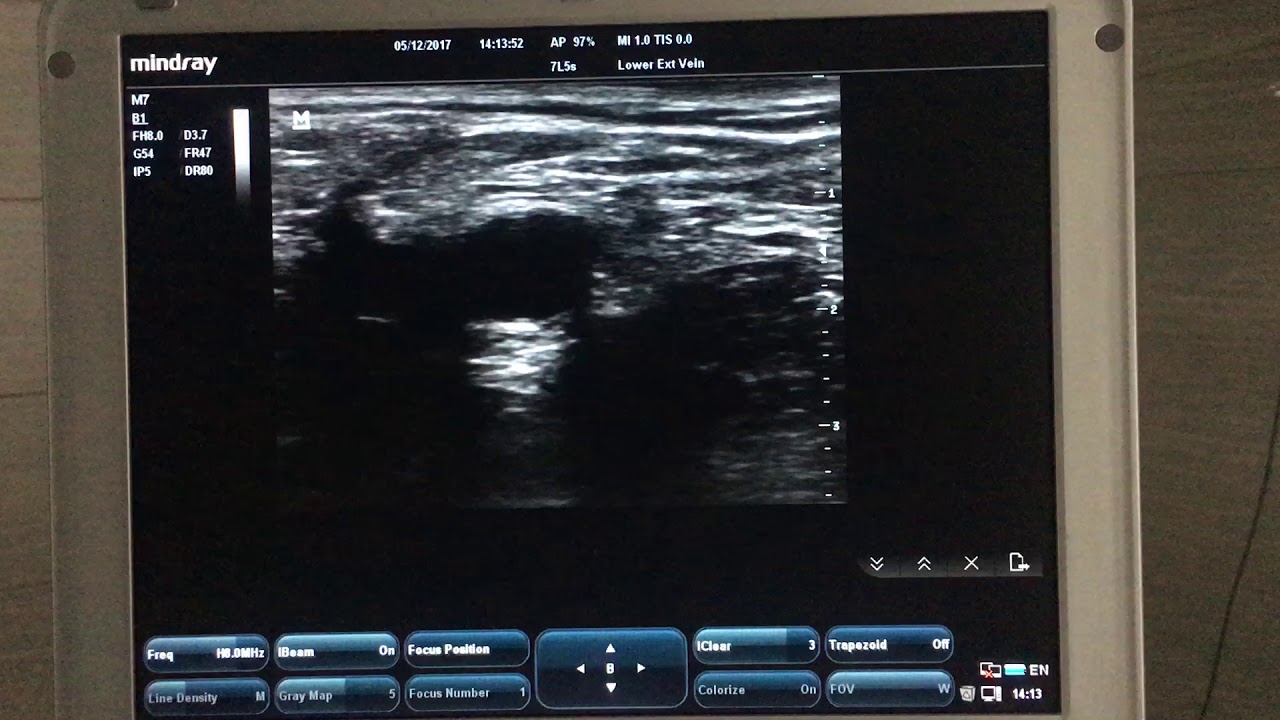

Узи нерва спб

Узи нерва спб 112 фото